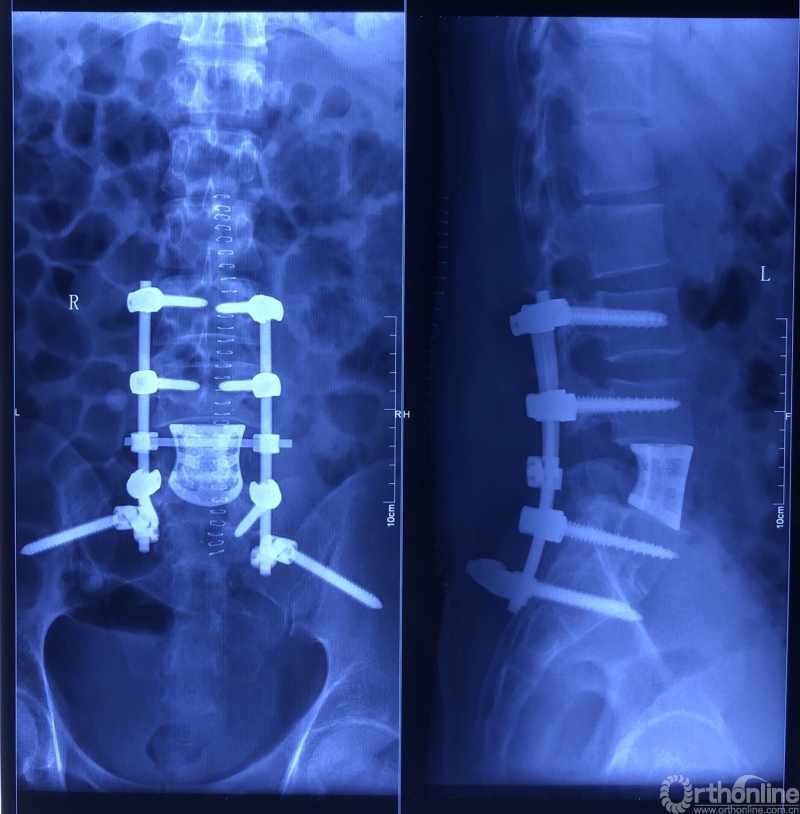

术后X线片